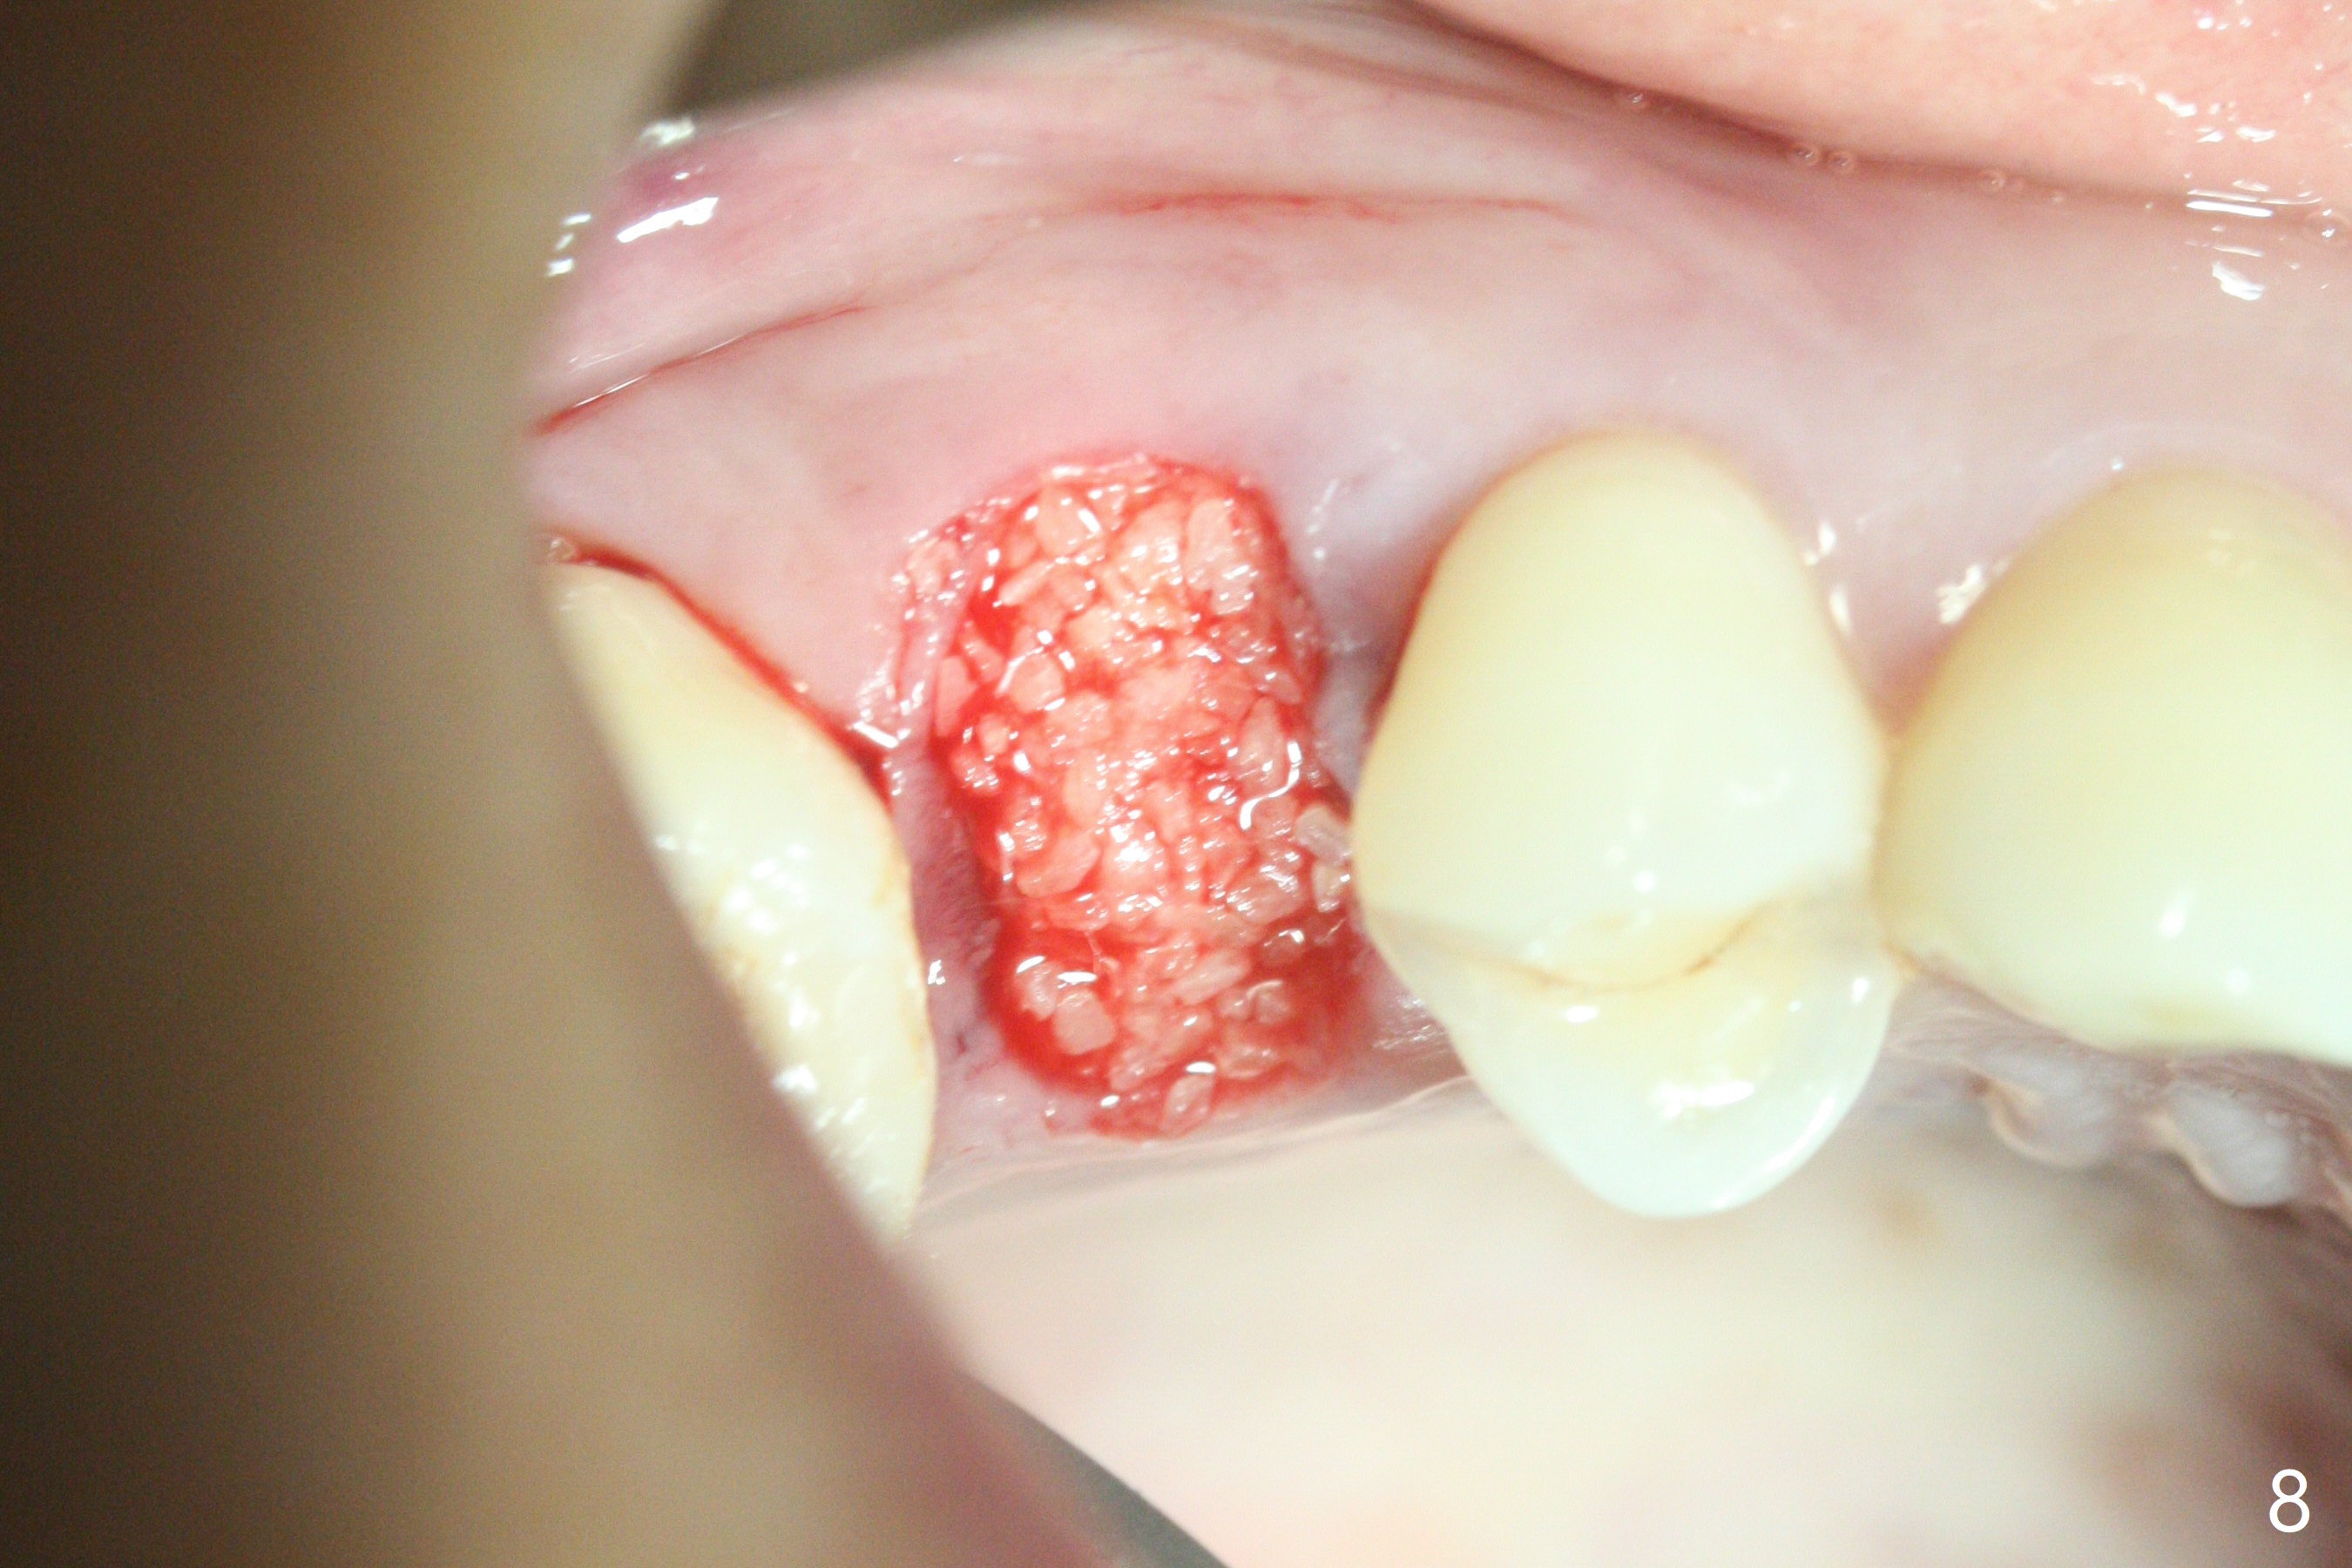

40岁女右上5近中龈下龋齿(图一),要求拔除植牙,上颌窦底板已经破坏穿孔,但是窦膜完整(图二)。清创后,放置PRF膜和粘性骨粉,用挖匙和上颌窦充填器尽量往上面推。然后放置导板,使用2.2x7.3 和3.0x7.3毫米钻头完成钻洞,可能无意中把骨粉推入上颌窦,之后利用报废植体(图三,四)完成提升,同时修补根尖缺损(利用之前放置的骨粉,图四:*,与图五(术前)对比)。当报废植体取出时,植牙窝已经形成,再放入少量骨粉,植入同样大小(之前扭力高)正式植体(不同品牌,图六,七),这时扭力低,放置愈合帽和骨粉(图七,八),以及6-9个月吸收膜,使用牙周胶水固定(图九),最后牙周敷料。术中术后几个小时没有上颌窦膜破裂迹象。术后一周牙周敷料松动,造成不适,去除时,膜好像粘附于敷料一起去除,骨粉暴露(图十),使用树脂敷料固定。后者术后一个月去除,因为局部有臭味。术后4个月切开放置愈合基台(图十一),术后五个月放置修复基台(图十二),使用塑料袖取模。术后5.5月同时放置牙冠和基台,十分顺手,口内粘固,之后同时取出,除去多余粘固剂,然后拧紧30Ncm(厂家推荐35 Ncm),一切非常顺利,觉得拍摄X光片是多余的。美中不足的是开孔(access hole)偏腭侧(图十二;由于自由手植入植体,与设计对比)。